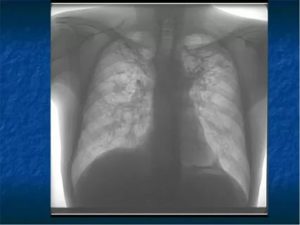

Фиброз легких характеризуется быстрой заменой здоровых клеток на рубцовую ткань. При распространении патология затрагивает бронхи, лимфатические и кровеносные сосуды, иногда прилегающие органы.

При диффузном фиброзе орган становится плотным и меньше в размерах. Газообменный процесс нарушается. В области поражения много коллагеновых волокон, появляются микроцисты.

- рентгенограмма необходима для визуализации легочного рисунка,

- компьютерная томография дает возможность увидеть очаговые, периферийные, субплевральные, сетевидные затемнения органа,